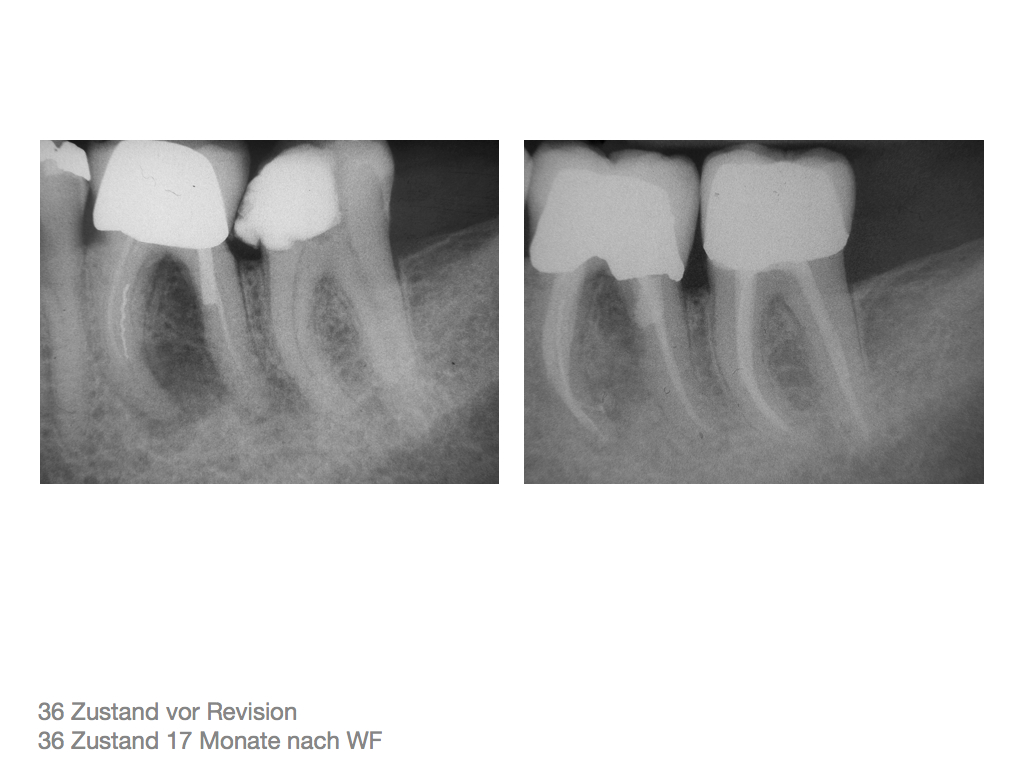

DMAWFR.007 Veröffentlicht 27. Februar 2012 am 1024 × 768 in Die Mutter aller WF – Revisionen – Recall nach 5,5 Jahren